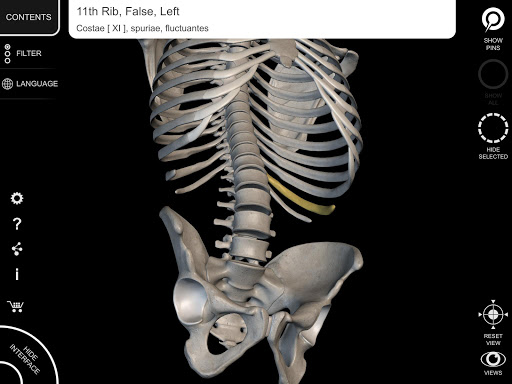

Mỗi xương của bộ xương người đã được tái tạo ở dạng 3D, bạn có thể xoay và phóng to từng mô hình và quan sát chi tiết từ mọi góc độ.

Bằng cách chọn mô hình hoặc ghim, bạn sẽ được hiển thị các thuật ngữ liên quan đến bất kỳ bộ phận giải phẫu cụ thể nào, bạn có thể chọn từ 12 ngôn ngữ và hiển thị các thuật ngữ bằng hai ngôn ngữ cùng lúc.

HÌNH GIẢI PHẪU 3D CÓ ĐỘ CHI TIẾT CAO

• Hệ thống xương

• Mô hình 3D chính xác

• Bề mặt của bộ xương có kết cấu độ phân giải cao lên đến 4K

• Xoay và Phóng to mọi mô hình trong không gian 3D

• Phân chia theo vùng để có hình ảnh rõ ràng và trực tiếp về từng cấu trúc

• Khả năng ẩn mọi xương

• Ghim tương tác cho phép trực quan hóa thuật ngữ liên quan đến mọi chi tiết giải phẫu